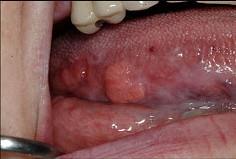

问题 以下关于舌癌(如图)的叙述,哪项是错误的()

选项 A.以鳞状细胞癌多见 B.多发生于舌缘,恶性程度高 C.常发生早期颈部淋巴结转移 D.舌根部癌可向茎突后及咽后部的淋巴转移 E.转移途径多为直接浸润和种植转移

答案 E